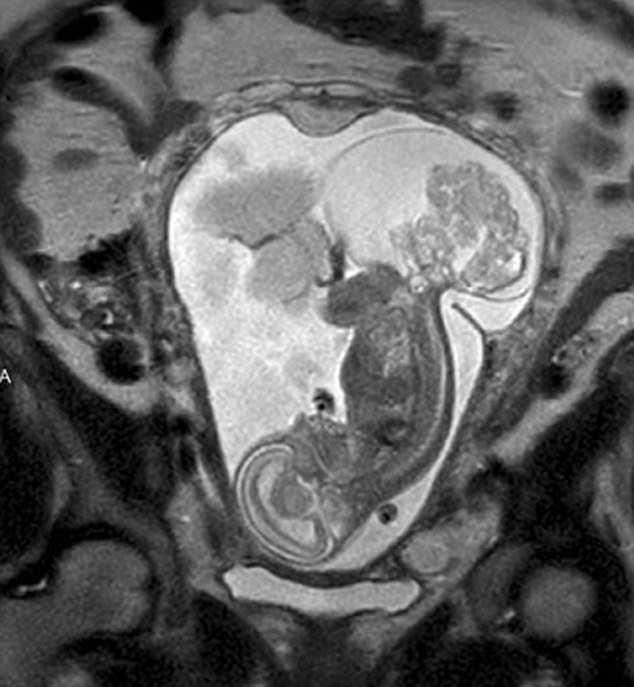

ݐݑGOIJpˑHqYäKVpL1023pːäoijb^ťYz{S픫q(Margaret Boemer)I16Wȓtޤ]LV~ޔV䬥AA~gNL|ġo~JޓNeEc~f{ɤeK12WALi|͐

ݐz{SKsȶsլȒԤtLͩ}}^LKؐtޔDnK٥]˳oRթؕҤΐࡲHȤByַ޸~ޭLe23Wȸ~Σʡଥ͔@z{SޭY٭LZ_ޓ~NL|ġo~AIEcޔȪ~ߔ·ɤWLoeNtA~\~ޓʡީvZ_YZ|K~JAkࡲz{S

ݐݬͱNL|20AmIEyc12WA޸}}i|͐z{SKLolvVYʣ[|͒ɐEVVZ|_أާ@ةӕңVIࡲ(taħM fYw)